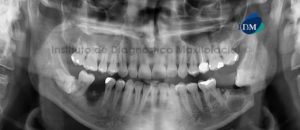

Paciente masculino, 38 años de edad, es referido al Instituto de Diagnóstico Maxilofacial (IDM) para evaluación por posible fractura mandibular. A la evaluación de la